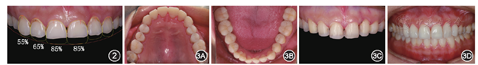

面下1/3高度未见明显降低;开口度正常,开口型有偏斜,双侧关节区、颞肌、咬肌无明显压痛,关节载荷实验无任何紧张和疼痛不适。唇齿关系:下颌姿势位上中切牙位于唇下0.5 mm,中位笑线,微笑时上前牙连线平直与下唇弧度不协调。口内检查:上前牙腭侧和后牙

面磨耗,磨耗面为光滑、圆钝的浅凹或杯状凹陷,磨耗导致牙本质暴露、上前牙变短、后牙接触区面积减小。多数牙齿(除下前牙外)邻面龋坏或有充填物。上前牙龈缘曲线不协调(22龈缘位置略高),下中切牙扭转,42、43融合牙(图1)。

咬合功能和美学效果的诊断和评价:患者初戴诊断饰面时偶有双侧耳前区轻度不适及夜间紧咬牙,2~3周后主观症状完全消除,咀嚼功能提高。锥形束CT示增加垂直距离后关节前后间隙较治疗前无明显改变(图4)。戴用9个月后牙齿咬合关系无明显变化,表明颌位关系稳定,双侧上颌尖牙有部分崩脱和磨耗,提示侧方咬合时引导牙尖的引导斜面斜度偏大,需要调整。而上前牙牙齿形态和排列还需进一步调整。根据功能和美学的调整要求,制作临时冠,确定上前牙最终形态(图5)。

尖牙引导(图8)。